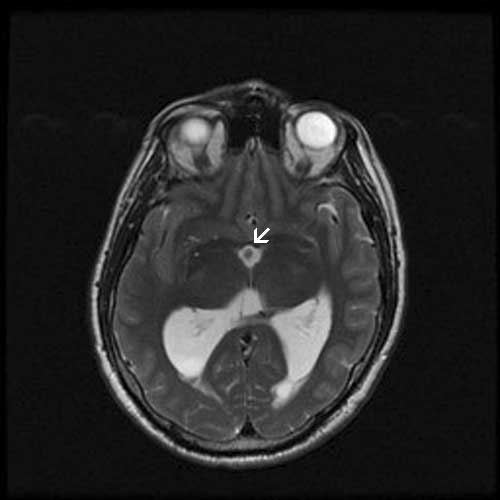

History: The patient was a 53 year-old man who presented with a 3 week old history of headache associated with walking and vision changes. Imaging studies demonstrated prominent dilation of lateral ventricles and a cyst in the third ventricle. On MRI scan, the cyst is 13 x 9 x 9 mm and is located at the roof of the third ventricle. It has an enhancing mural nodule. The cyst was removed and generated the specimen here.

MRI T2